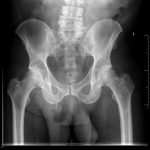

Significant findings:

The AP and lateral pelvis x-rays revealed two sewing needles, 60 mm in length, within the soft tissue over the anterior right lower hemipelvis. In addition, the AP view showed emphysema involving the right hemiscrotum (arrow), concerning for perforated bowel.

In this case, the patient attempted to drain the suspected abscess with a needle, resulting in bowel perforation. The sensitivity for plain abdominal radiographs to detect needles in the peritoneal cavity varies by needle size. In a study of retained surgical needles, radiographs had a sensitivity of 99% for needle size greater than 25 mm.4 Although plain radiographs are not as sensitive as multi-detector computed tomography in the detection of free air, a recent retrospective study showed a sensitivity of 80.4%. The study was limited in that only 8.8% of perforations involved the small bowel or colon.5 Due to free air seen on x-ray, the patient was taken to the operating room where a cecal perforation was noted in addition to the incarcerated inguinal hernia.